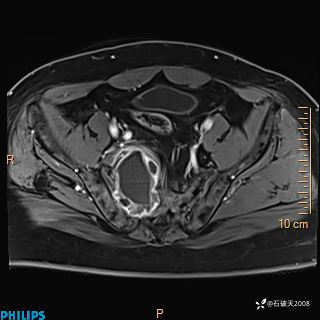

现病史:7个月前患者因骶尾部占位就诊于北京大学人民医院,MRI示:骶骨右侧及右骶前占位,考虑骨巨细胞瘤可能,动脉瘤样骨囊肿可能,神经源性肿瘤待排。行手术治疗,术后病理回示:XXXXX。术后给予对症治疗,具体不详,恢复良好。近几个月反复出现发热,伴骶尾部不适,多次住院给予对症治疗,2天前患者无明显诱因再次发热伴骶尾部不适,无大小便失禁,为求进一步治疗,遂门诊来我院,在门诊初步检查后,以“骶尾部肿物”为诊断收入我科。入院来患者神志清,精神一般,饮食睡眠可,大小便无明显异常,体重无下降。

2023年3月份MRI影像

增强轴位